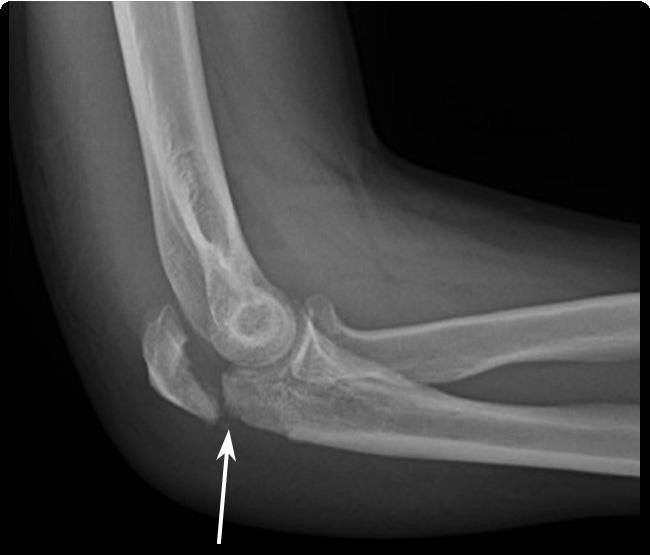

+ Diagnóstico y Tratamiento de Lesiones Deportivas:

Atención especializada para esguinces, desgarros musculares, lesiones en ligamentos y fracturas relacionadas con el deporte.

+ Atención de Fracturas y Lesiones Traumáticas:

Diagnóstico, reducción y tratamiento de fracturas, luxaciones y traumatismos óseos.